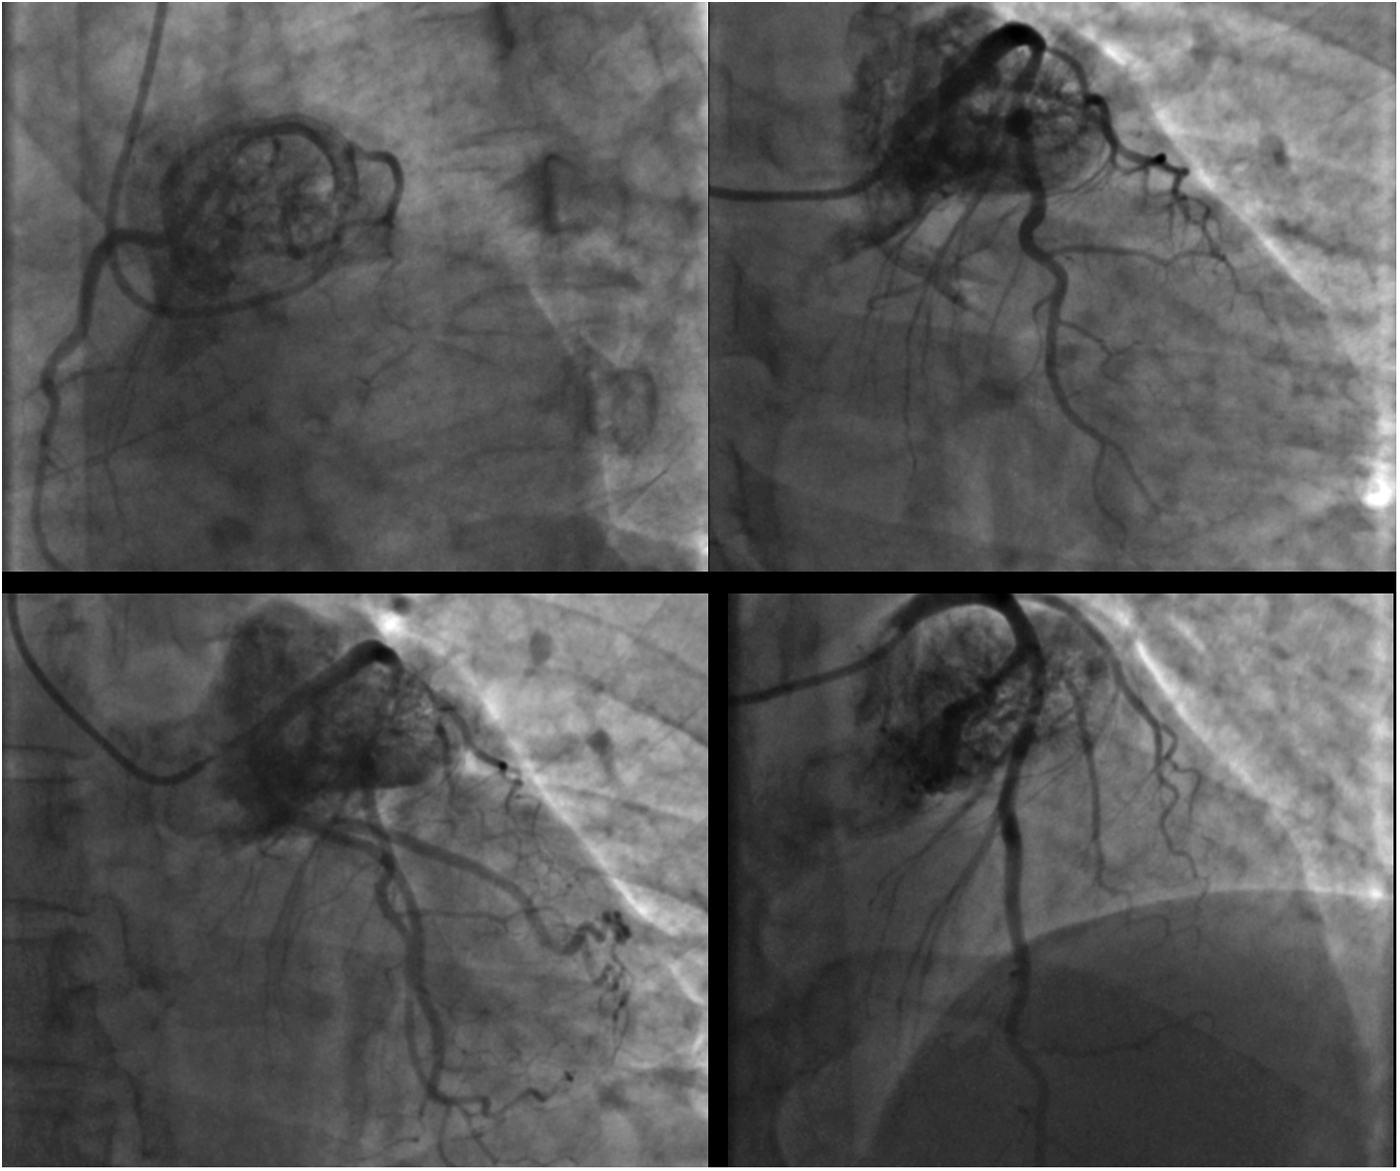

A 46-year-old man, a candidate for aortic valve replacement, was referred to us after an invasive coronary angiogram (ICA; Figure 1; Supplementary Movie 1) showed a large cardiac mass encasing the left coronary artery; there was no coronary artery stenosis. The patient presented with a family history of atherosclerotic coronary artery disease, hypertension treated with lecardipine and lobizide, type 2 insulin-dependent diabetes mellitus, and obesity (BSA = 2.10 m2). The patient provided written informed consent for this study.

Figure 1

Coronary angiogram in different oblique projections showing a large cardiac mass encasing the left coronary artery.